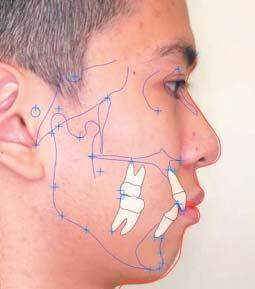

• Mixed dentition stage with Class II Division I incisor relationship • Late dental development as multiple deciduous teeth such as 53, 54, 55, 63, 64, 65, 73, 74, 75, and 85 are still present at his age • Complete deep bite to palatal mucosa • Increased anterior overjet of 8mm • Bimaxillary proclination • Gummy smile • Upper dental midline deviation to the right by 1mm and lower dental midline deviation to the right by 3mm • Class I permanent molar relationship on both sides • OPG shown incipient developing crowding on 13, 23, 33, 43, 17, 18, 27, 28, 37, 38, 47, and 48 • Lateral cephalometric analysis showed retrognathic mandible with slight maxillary prognathism • Skeletal Class I tending to Class II relationship • Slightly high mandibular plane angle • LAFH% lesser than the ideal percentage; indicates a discrepancy in the facial proportion • Approximately 90 degrees interincisal angles, with acute nasolabial angle and shallow labiomental fold

Figs. 1-8: Intra and extra oral images before treatment Fig. 9: Panoramic radiograph before treatment Fig. 10: Cephalometric radiograph before treatment Fig. 10

Figs. 16-23: Intra and extra oral images after treatment Fig. 24: Panoramic radiograph after treatment Fig. 25: Cephalometric radiograph after treatment Fig. 25

Fig. 31 Fig. 32

Figs. 31-32: Ortho analysis (before and after)